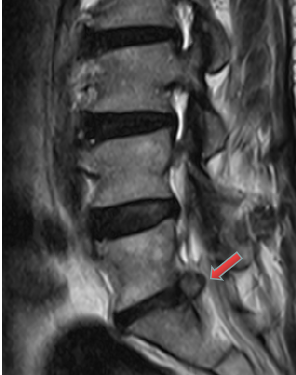

3月前,患者再次出現(xiàn)腰腿痛疼痛癥狀,夜不能寐,嚴重影響生活?;颊邚?fù)查了腰椎磁共振,結(jié)果提示:腰5/骶1椎間盤突出復(fù)發(fā),明顯壓迫神經(jīng)。經(jīng)過口服消炎止痛藥、理療等保守治療,患者腰腿痛無明顯改善,于是再次入住惠州三院脊柱外科,被診斷為復(fù)發(fā)性腰椎間盤突出癥。

核磁共振檢查影像